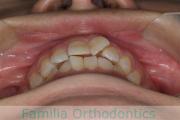

歯並びを治したいということで来院されました。下あごがやや右側に偏位して後退している、上顎前突(出っ歯)でした。上下左右から小臼歯を抜歯して、歯科矯正用アンカースクリューを併用したマルチブラケット法にて治療を行いました。約2年、24回の来院をしていただきました。

下顎の後退はいびきなどの上部気道の障害が出やすいと考えられます。